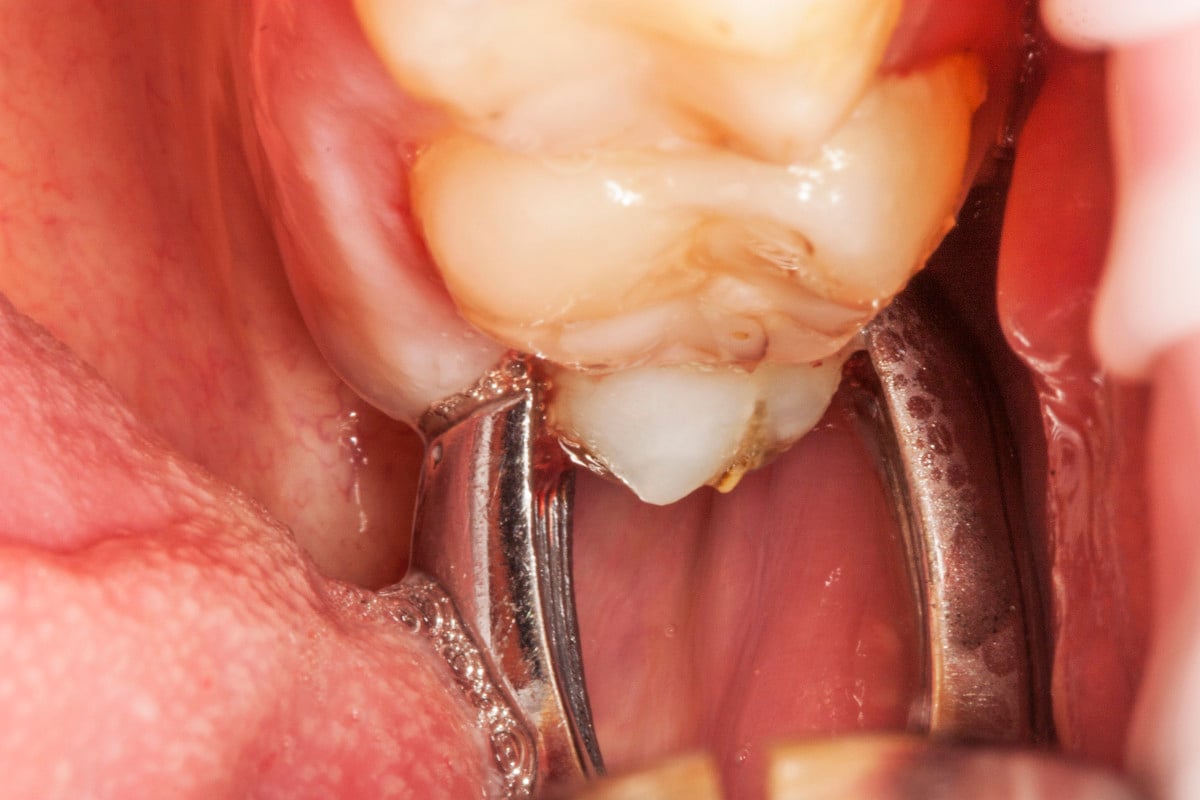

„Pacjent, który się zgłosił z dolegliwościami bólowymi górnej lewej szczęki, miał charakterystyczne objawy dla zapalenia ozębnej. Dzięki wykonaniu diagnostyki radiologicznej (zdjęcie pantomograficzne), ujawniono istnienie dziewiątego zęba, który był dodatkowo obciążony okluzyjnie. Pacjent miał otwarty zgryz – w momencie, kiedy zamykał zęby kontaktował się tylko na zębach trzonowych. To wszystko powodowało, że główny nacisk zębów był na tą malutką stożkową dziewiątkę. Przeciążenie tego zęba spowodowało to, że związanie włókien kolagenowych z podłożem kostnym osłabiło się, powstała kieszeń dziąsłowa i kieszeń kostna. To wszystko było przyczyną silnych dolegliwości bólowych o charakterze periotonditis, czyli zapaleniu wzdłuż calej długości ozębnej.

Pomimo, że ten ząb umieszczony w guzie szczęki, w miejscu bardzo odległym, niewidocznym i pacjent nie miał świadomości, że ma ząb dziewiąty, to zabieg był dość prosty, nie sprawiający kłopotów i nie wystąpiły żadne komplikacje.” –